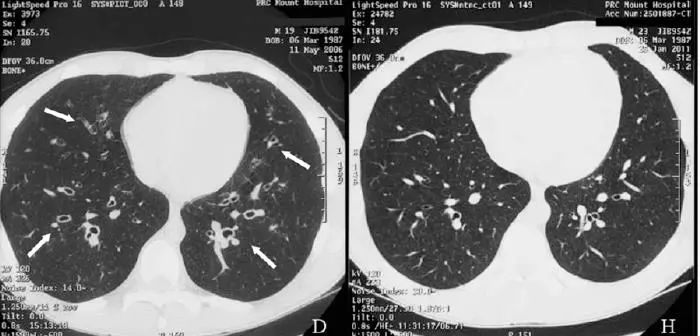

He adhered to treatment and significant improvement in symptoms was noted over 6

months. At a review 2 years later, he had complete resolution of symptoms and further improvement in spirometry values , and repeat high-resolution computed tomography showed no evidence of previously noted dilated airways.

病人坚持治疗,6月后症状好转,2年后,各方面都好转,连支气管扩张都好了!

This case highlights the fact that not all radiological postinfective bronchiectatic changes should be considered as irreversible.Early effective therapy should be provided and the patient monitored for resolution。

事实胜于雄辩,影像学发现的支扩,并不都是不可逆的。早期治疗,随访,有希望缓解。

下面是作者提供的精彩图谱,什么时候,国内的文献也有图,有稍微清晰一点的图。